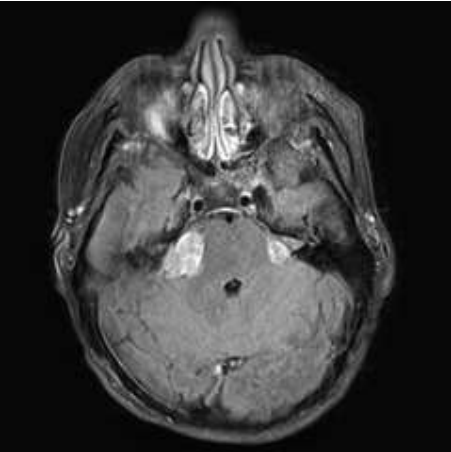

Paciente de 25 anos, sexo masculino, com histórico de perda auditiva e alterações do equilíbrio há 3 meses. A avaliação com ressonância magnética demonstrou a seguinte imagem:

Assinale a alternativa correta